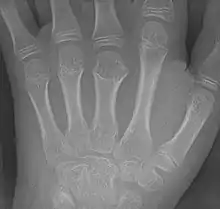

Brachymetacarpia of the third metacarpal (middle finger)

Brachymetacarpia or brachymetacarpalia is a medical condition in which the metacarpal bones of the hands are shortened.[1] The equivalent condition in the foot is brachymetatarsia, in which the metatarsal bones are shortened. Brachymetacarpia is typically congenital and presents in childhood or early adolescence, but it can also be associated with other acquired syndromes or endocrinological conditions. While cosmetic appearance is the most common concern of affected individuals, brachymetacarpia may also affect hand function due to alterations in muscle and tendon length. Treatment usually involves lengthening of the affected bone(s), either acutely with a bone graft or gradually with an external fixator.[2]